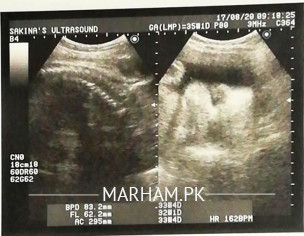

Plz see my wife's report. Docror said that the baby is not growing with normal pace. She is givong us signs of possible c section. We have shown this report to many other doctors in canada and pak and everyone said baby is growing normal. Plz help should we change the doc or go for c section.

follow AFI. if it gets below 5, then its worrisome. for now, the report is normal